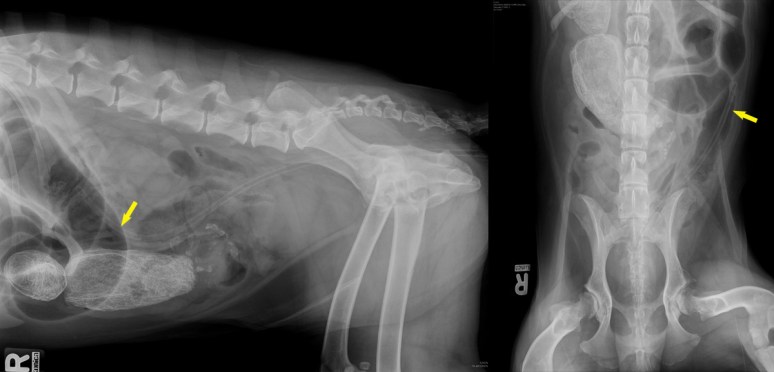

D’abord, une sonde a été glissée dans le colon pour en déterminer la localisation (flèches) et vérifier que les structures minérales étaient dans un segment du petit intestin. Une écho a aussi été faite, puis un CT. Puis, le chien a été envoyé en chirurgie (cliquer sur les images pour obtenir plus de détail).